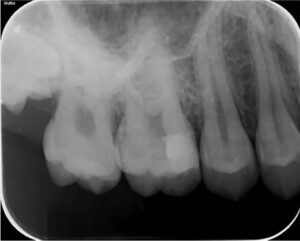

治療直後

歯髄保存療法直後のレントゲン写真です。矢印の部分がMTAセメントで、その外側はコンポジットレジンで緊密に閉鎖しています。